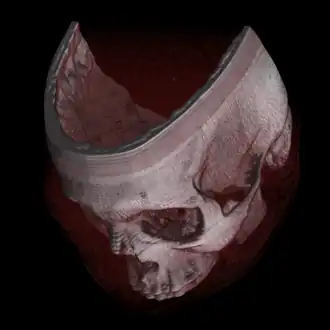

Volumerendering is het weergeven van volumetrische informatie op het beeldscherm. Anders gezegd: gegevens over een 3D-object worden vertaald naar waarden die als kleur op het beeldscherm getoond kunnen worden. Het speciale van volumerendering is dat alle gegevens van het 3D-object bijdragen aan de uiteindelijke weergave op het scherm, dus niet alleen de gegevens aan de buitenkant van het object. Omdat ook gegevens binnenin het 3D-object bekend zijn, is het nu ook mogelijk om binnenin het object te kijken. De term komt uit het vakgebied "computergraphics en datavisualisatie".

Volumetrische data geven informatie over een driedimensionaal object (bijvoorbeeld een kubus). De data zijn volumetrisch, omdat de verzameling gegevens niet alleen iets zegt over de buitenkant van het object, maar ook informatie bevat over de binnenkant van het object. Een gebied waar volumetrische data worden gemeten, is in de medische wereld. Bij het uitvoeren van een CT-scan, of een MRI-scan zijn juist de gegevens over het binnenste van het menselijk lichaam belangrijk.

Bij directe volumerendering worden de volumetrische data niet eerst vertaald naar geometrische primitieven, maar wordt de informatie over het 3D-object direct gebruikt om het object weer te geven. Een voordeel hiervan is dat de 3D-gegevens niet verloren gaan, maar allemaal gebruikt worden.